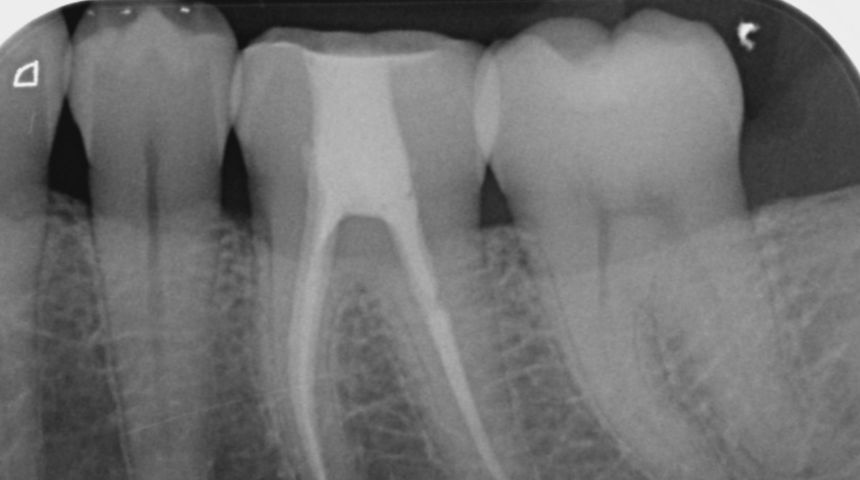

Take a look at some of our recent cases below!